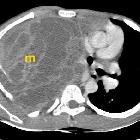

Ewingsarkom der Brustwand

Ewing sarcomas tend to be large with poorly marginated tumors, with over 80% demonstrating extension into adjacent soft tissues. It should be noted that pPNET often extend into bone, making the distinction difficult.

Plain radiograph and CT

The appearance of these tumors is very variable, but they usually have clearly aggressive appearance. Common findings include :

- permeative: 76%

- lamellated (onion skin) periosteal reaction: 57%

- sclerosis: 40%

They occasionally demonstrate other appearances, including Codman triangles, spiculated (sunburst) or thick periosteal reaction and even bone expansion or cystic components.

Soft tissue calcification is uncommon, seen in less than 10% of cases .